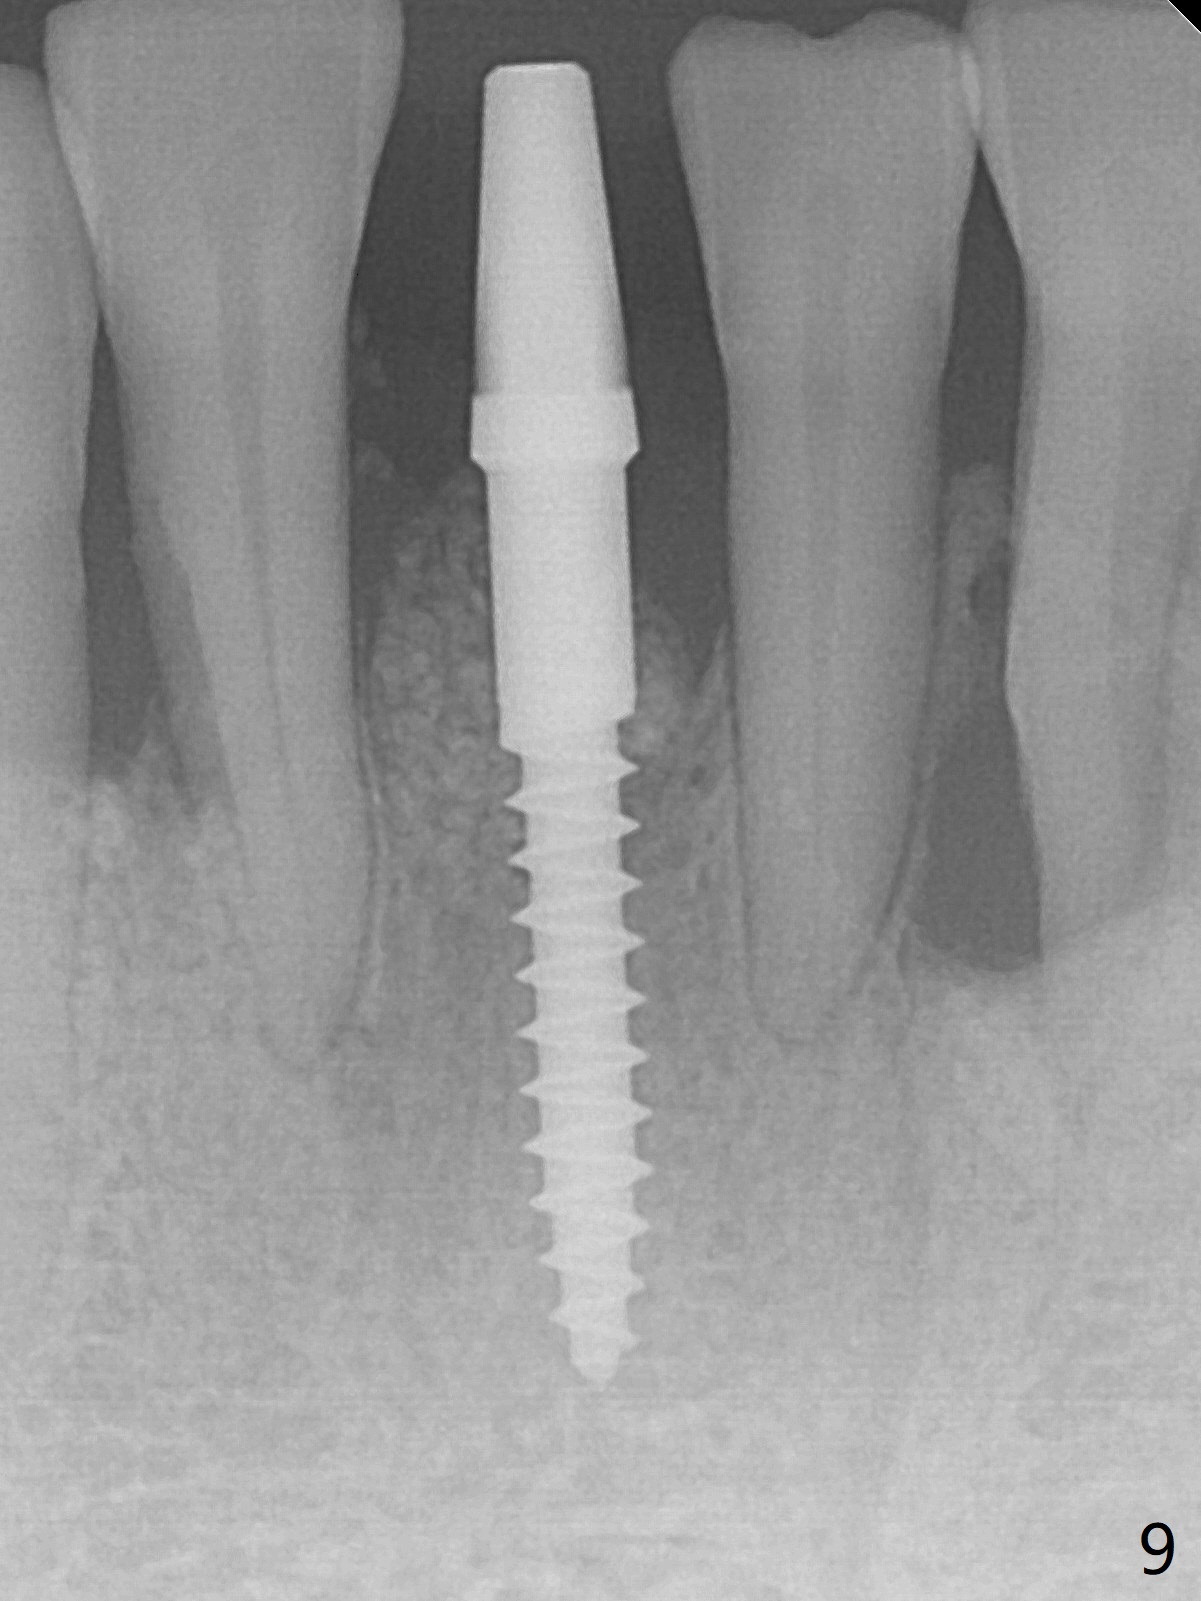

There is gingival inflammation at #25 buccally (Fig.1) and lingually (Fig.2). The bone loss is severe (Fig.3). Soft and hard tissue heights are 5 mm (cuff will be 4 mm) and 10 mm (implant will be 12 mm with 2 mm outside the native bone, Fig.4). The apex of the affected tooth appears deviated distal (Fig.5 *). The initial osteotomy happens to follow the long axis of the socket (Fig.6); to establish a correct trajectory, a new osteotomy should be made at the site labeled as a red line. In fact it is executed as planned (Fig.7). Because of the narrow flat ridge buccolingually, a 2.5x12(4) mm 1-piece implant is placed with >40 Ncm (Fig.8). With deeper placement of the implant, Vanilla graft is placed in 2 steps (Fig.9,10). The patient will return 2.5 months for extraction and implant of the fused teeth #22 and 23. No implant threads are exposed 10 months postop (Fig.11). CT taken 11 months postop shows that the 2.5 mm implant is in the middle of the bone (Fig.12) or 2 years post cementation (Fig.13).